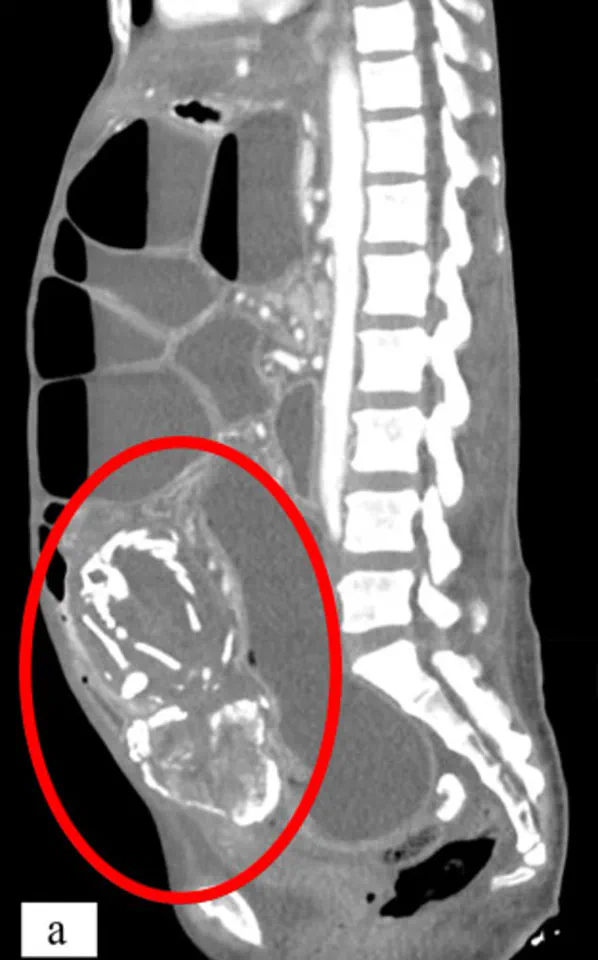

The process begins with an ectopic pregnancy, a condition where the embryo implants outside the uterus. Around 1 in 11,000 pregnancies fall into this category, and while most ectopic pregnancies occur in the fallopian tubes, some develop in the abdomen, ovaries, or even at the site of a previous C-section scar. When these pregnancies fail, the maternal body typically reabsorbs the tissue. However, if the fetus is more than 12 weeks old, its skeletal structure—which now contains bone—becomes too large to be absorbed. The immune system then encases the dead fetus in calcium, a form of biological mummification, creating a 'stone baby' that can remain in the body for decades.

The consequences of lithopedion extend far beyond the physical. Cases where the condition goes unnoticed for years often result in severe symptoms, including chronic abdominal pain, gastrointestinal issues, or even pelvic infections. In extreme cases, the mass can compress vital organs, leading to malnutrition, intestinal blockages, or cardiac arrhythmias. One tragic example involved a 50-year-old woman from the Congo who carried a lithopedion for nearly nine years before her death in 2023. Misdiagnosed and believing her condition to be a curse, she refused treatment until her body could no longer sustain her.